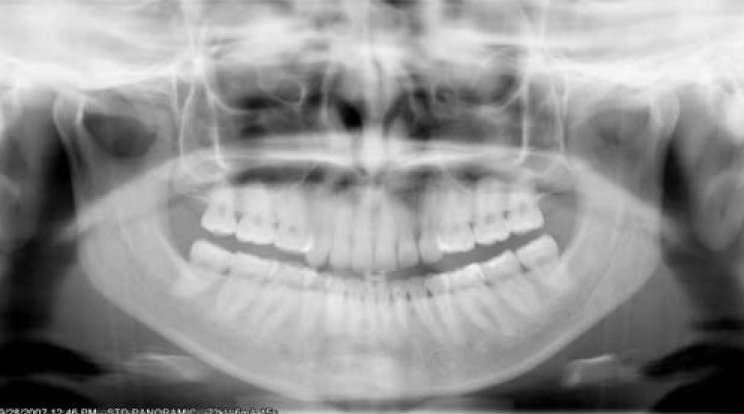

The smile line is exaggerated, the mandibular incisors appear blurry and elongated, and the condyles are cut off

Chin tipped too low